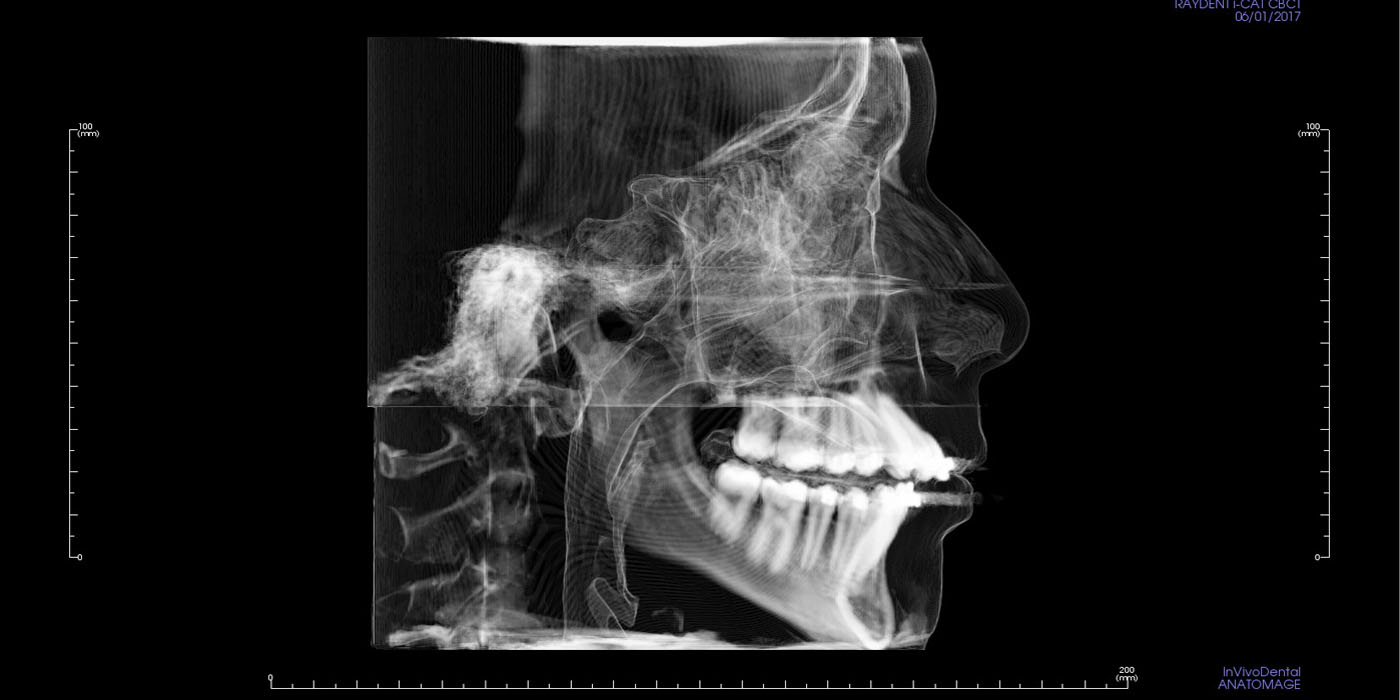

Lateral Cephalogram

The lateral cephalogram is a profile x-ray of the skull and soft tissues and is used to assess the relation of the teeth in the jaws, the relation of the jaws to the skull and the relation of the soft tissues to the teeth and jaws.

In children, growth predictions can be made and we can also determine the changes that have occurred with treatment. In adults, treatment can be predicted with varying degrees of accuracy and results quantified.